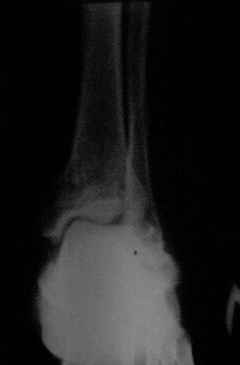

Уважаемый Дмитрий! Можете ли Вы добавить аксиальные проекции!

Присоединяюсь к мнению Я.Одесского о необходимости аксиальных снимков и, наверное, сразу снимков по Бродену (через каждые 10 градусов внутренней ротации стопы). Кроме этого необходима КТ. Она позволит уточнить срослись переломы или нет. Соответственно и тактика: если не срослись можно попробовать АВФ; если срослись -артродез.

С левой стопой дело похуже. Нужен прямой снимок, да и боковой не помешает повторить на всю стопу, ну и плюс аксиальный. Готовтье аппарат.

Отправляю снимки(свежие)и фото стоп.

С уважениемД.Б.